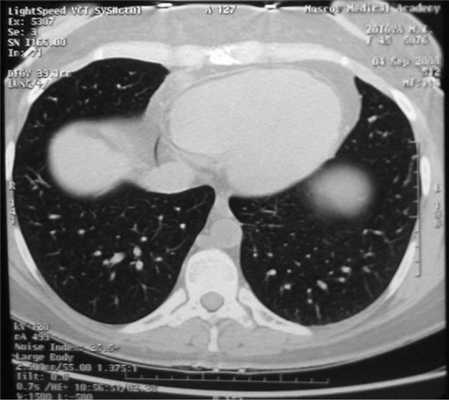

Все больные были разделены на группы в зависимости от размера очагового образования: 1-ю группу (диаметр ООЛ 0,5-1; рис. 1) составили 9 мужчин и 14 женщин, 2-ю группу (диаметр ООЛ 1-2 см; рис. 2) - 30 мужчин и 13 женщин, 3-ю группу (множественные ООЛ; рис. 3) - 27 мужчин и 17 женщин.

Рис. 3. Компьютерная томограмма груди пациента 3-й группы.